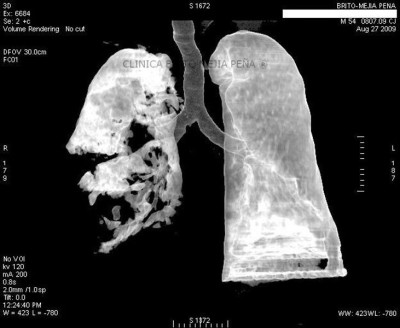

Trombosis arteria pulmonar 3D

Post Image